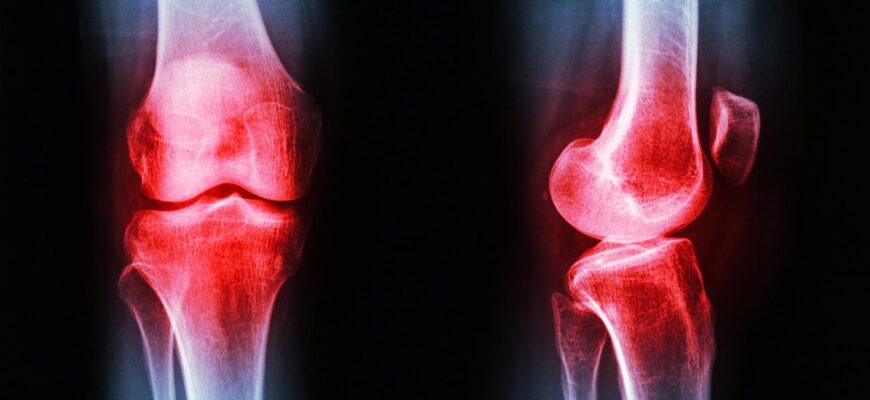

Ревматоїдний артрит (РА) — хронічне системне аутоімунне захворювання, що уражає ~1% населення Землі (~20 мільйонів людей). Його суть: імунна система атакує синовіальну оболонку суглобів — і запалення поступово руйнує хрящ і кістку. Поточне лікування включає метотрексат, біологічні агенти та глюкокортикоїди — ефективні, але з тяжкими побічними ефектами при тривалому застосуванні. Пошук нових мішеней і речовин із природних джерел є одним із головних напрямів ревматологічних досліджень.